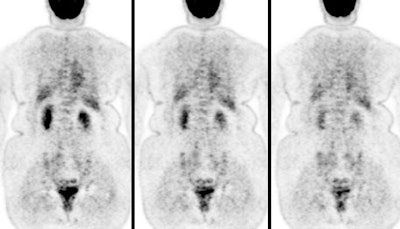

FDG PET exam results in breast cancer patient guide therapy: The patient shown below was a 40 year old female who had undergone lumpectomy and adjuvant chemo/radiation therapy for breast cancer. Ten months later the patient began to experience pain in the right shoulder. A bone scan and CT scan were interpreted as negative. The FDG PET exam revealed numerous foci of tracer accumulation within the right axilla and chest consistent with metastatic disease. As a result of the PET exam findings the patient was treated with another course of chemo/radiation therapy. The exam was performed on a Siemens ECAT EXACT PET scanner; 10 mCi FDG, and 5 bed positions. Case courtesy of Rush-Presbyterian-St. Luke's Medical Center, Chicago, IL and CTI. |

|